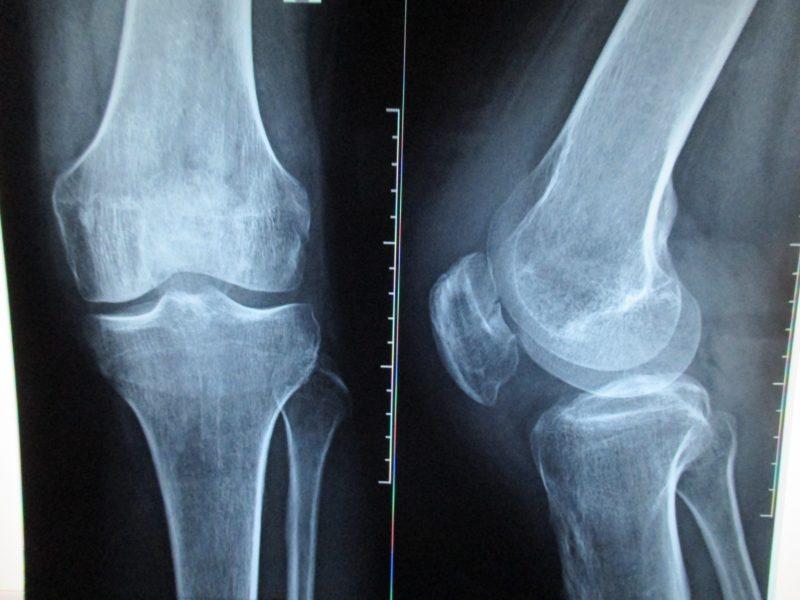

Сначала врач осуществляет общий осмотр пациента, собирает анамнез, изучает жалобы и пытается выяснить, почему ноги не разгибаются в коленях. Затем назначаются лабораторные исследования, включая общие анализы крови и мочи, биохимический анализ крови и тест на ревматоидные факторы.

Что касается инструментальной диагностики, пациентам рекомендуется пройти рентгенографию, а при необходимости уточнения диагноза — компьютерную или магнитно-резонансную томографию.